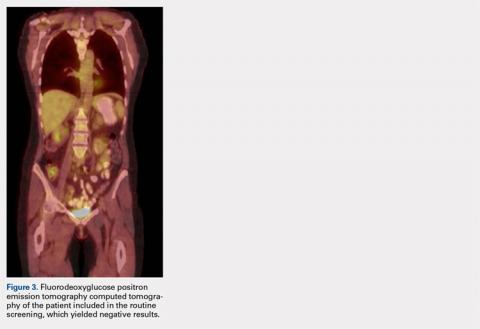

MRI of the foot and ankle was reviewed and demonstrated a large soft-tissue mass over the medial aspect of the ankle extending posteriorly to engulf the medial flexor tendons and medial neurovascular bundle (Figures 2A-2C). Interestingly, the radiologist’s report only mentioned a “large region of devitalized tissue underlying the known medial ankle ulcer which extended to the tibiotalar and subtalar joints and bone marrow changes in the talus most compatible with osteomyelitis.” FDG PET-CT images from the patient’s past 2 years were reviewed, and the radiologist was contacted to confirm the negative findings. Unfortunately, FDG PET-CT performs no routine imaging below the elbow or knee when evaluating for this particular malignancy (Figure 3).At presentation, our differential diagnosis included recurrence of the malignancy, secondary malignancy, infection, and inflammatory disease. After a lengthy discussion with the patient and consultation with our institution’s musculoskeletal oncologist, the decision was made to perform a right-ankle mass biopsy and marginal excision with wound irrigation and débridement and tarsal tunnel release.

Pathology was finalized as a recurrent, EBV-positive, and nasal-type ENKTL. The patient underwent bone marrow biopsy, which yielded negative results. CT of the chest, abdomen, and pelvis were negative for the disease. FDG PET-CT, which included the extremities, was performed and demonstrated increased uptake in the right ankle, consistent with the malignancy (Figure 4).